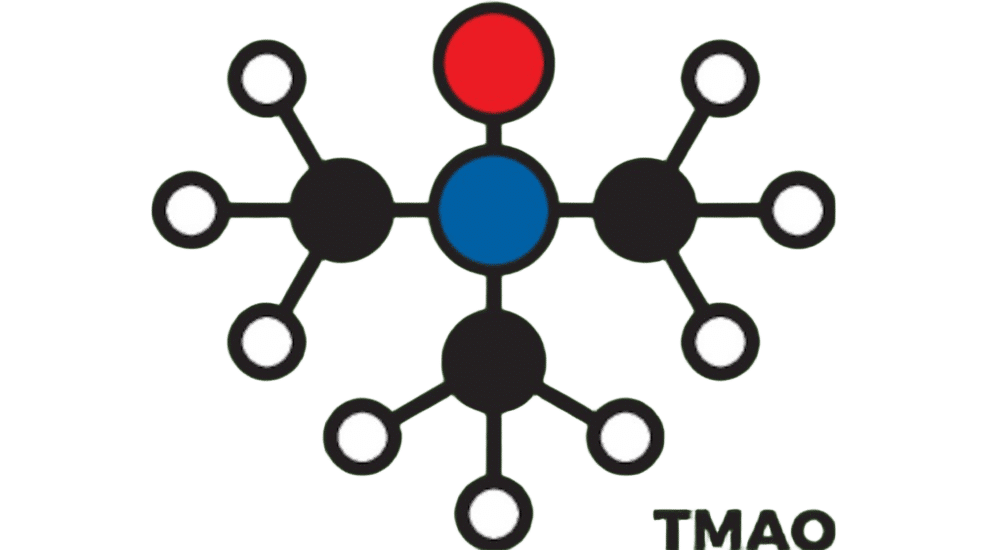

La métabolomique permet de découvrir de nouveaux biomarqueurs métaboliques. Un exemple intéressant est celui de...